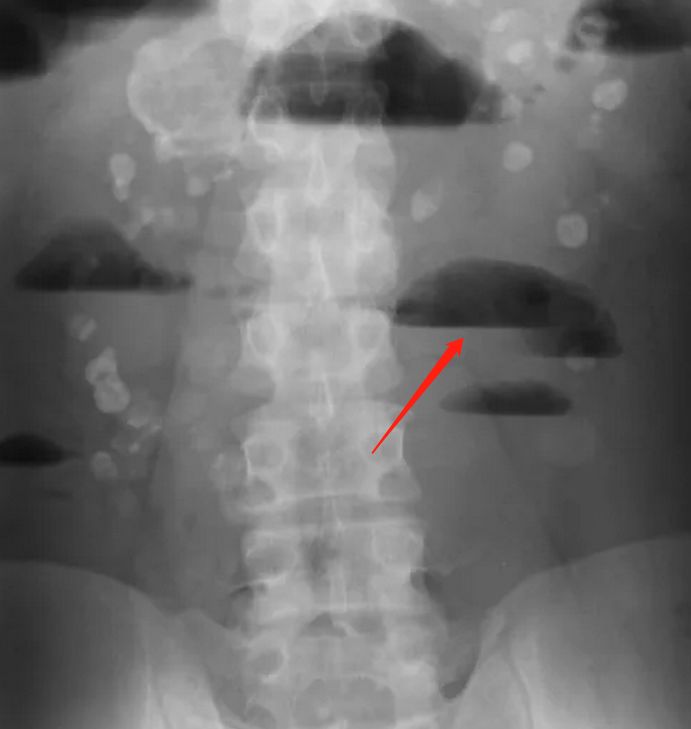

肠梗阻是常见的外科急腹症,“痛、吐、胀、闭”是其典型的临床表现,而其X线表现,外科教材基本都是这样描述:肠 梗阻4~6小时后,腹部立位X线检查即可见胀气的肠袢及多数气液平面。可见气液平面对于诊断肠梗阻非常重要,那么问题来了,什么是气液平面?肠梗阻一定出现气液平面吗?……

气液平面是一种X线检查的征象,属于放射学名词,是指气体和液体相连接的水平分界线。气液平面可见于各种原因引起的气体和液体同时存在的疾病,并不特异的出现在肠梗阻中。

由于肠腔积气积液导致肠管扩张,腹部站立位X线检查可见梗阻部位以上出现高低不等,宽窄不一的气液平面,X线诊断肠梗阻即是基于肠腔的扩张形态和气液平面。